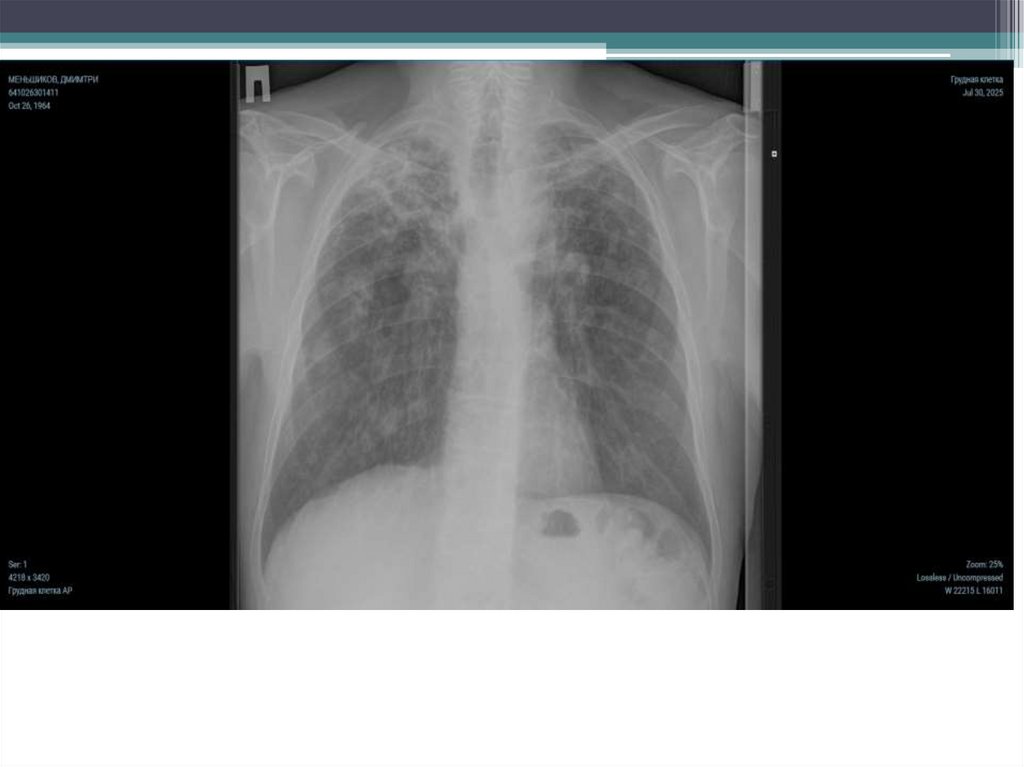

• Меньщиков

Дмитрий

Дмитриевич

• 26.10.1964

• Диссиминирован

ный

хронический

туберкулез

легких в фазе

распада МТ(+)

ЛЧТБ НС I

категория IА

группа ДУ.

Обзорная

Рентгенография

ОГК от

20.01.2025г